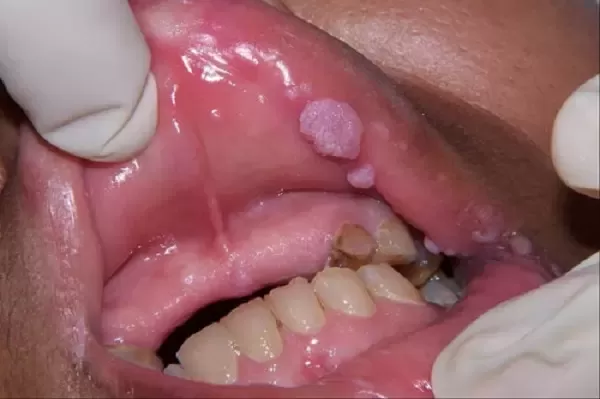

Mọc những mụn li ti màu trắng hoặc đỏ ở môi và viền môi. Những nốt mụn này không gây đau, không ngứa rát. Chúng mọc độc lập và có bề mặt trơn nhẵn.

Sau một thời gian, mụn mọc dày hơn thành từng mảng hình như hoa lơ và mào gà.

Khi bệnh phát triển nặng, sùi mào gà sẽ lây lan vào cả khoang miệng.

Hình ảnh sùi mào gà ở môi giai đoạn đầu